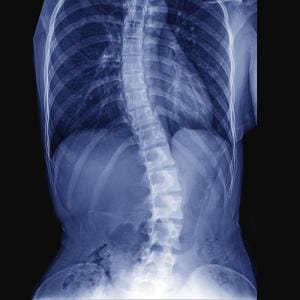

Throughout our lives, we have physical stress on our body, some acute such as falls, traumas, accidents and some chronic such as sitting for long periods, working at a desk for long periods, using computers or phones or standing for long periods. These physical stresses cause us to lose the normal alignment and put the spine in a weakened position. At first, this causes no pain but as it continues to abnormally load the spinal structures, it begins to break down the spinal structures leading to spinal damage and eventually the pain and functional loss to develop.